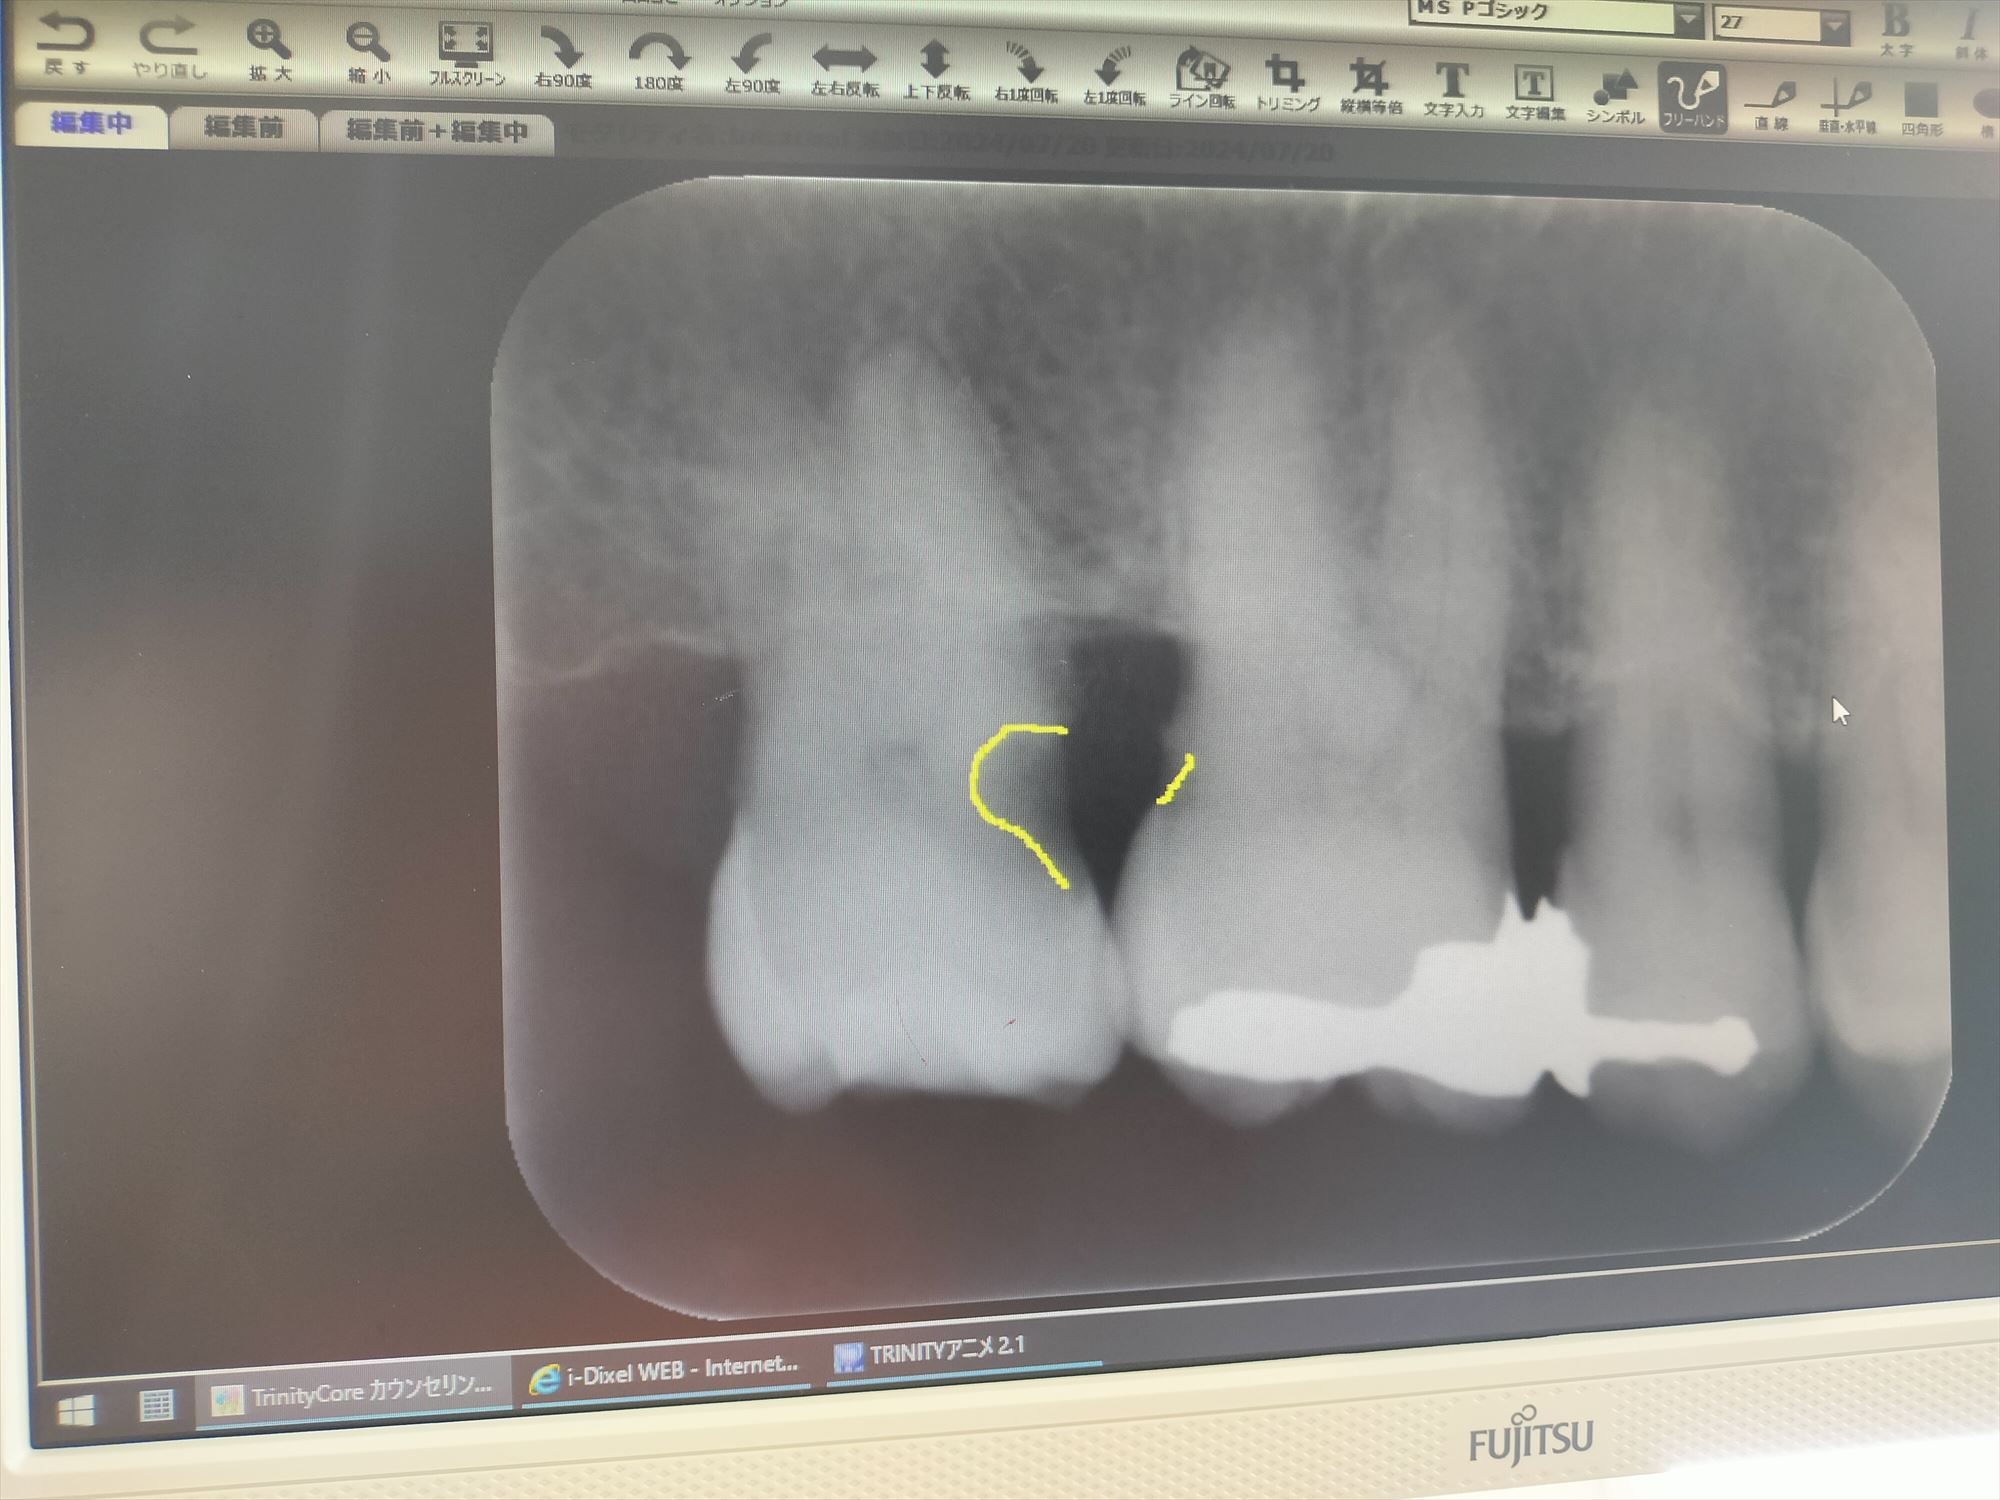

2024年7月5日(金) 右上奥歯の虫歯が痛んだ

2024年6月7日(金) 銀冠